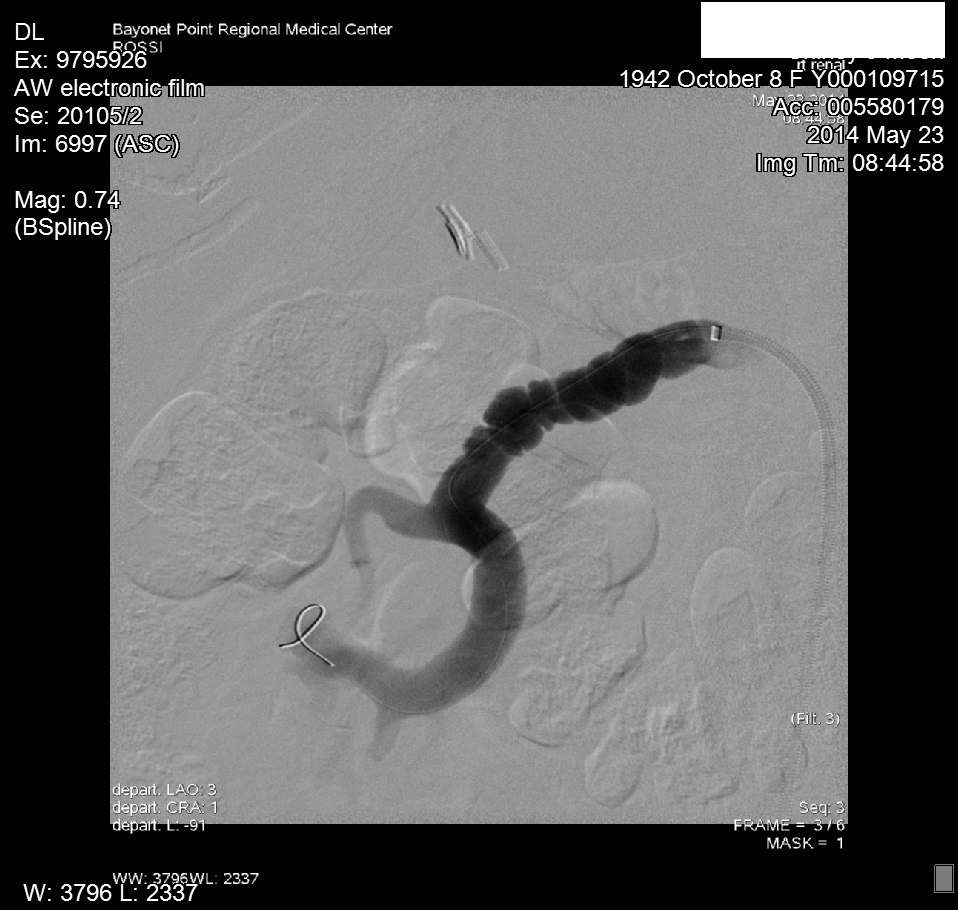

Upon obtaining the abnormal doppler findings, our interventional cardiologist performed an abdominal angiogram with selective bilateral renal arteriography. The angiogram demonstrated diffuse right renal artery haustra consistent with FMH. As well, abnormal retograde filling of the right renal vein and IVC was noted, and consistent with an AV fistula within the right renal artery helium (Figure 4). The left renal artery was normal on preliminary imaging, but remained suspect. Upon IVUS (Intra Vascular Ultra Sound) imaging, a significant (20mm) gradient was noted within the left distal renal artery.3 Bilateral cutting balloon angioplasties were performed and the patient was then sent to CPRU for recovery (Figure 5 & 6).

Figure 5 Angiogram images of RRA FMD.

Figure 6 Angiogram images of RRA FMD.